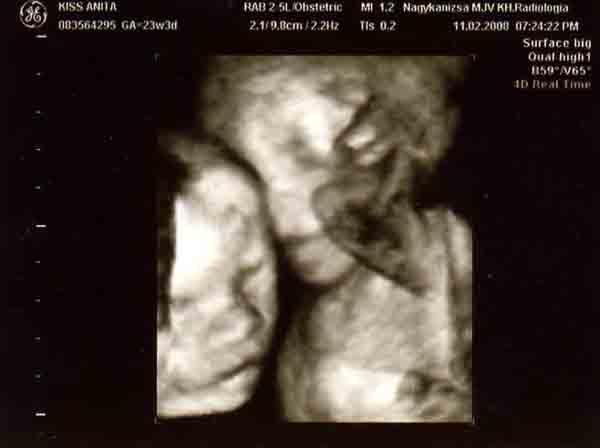

Banika: nagyon jok lettek a kepek!!! Olyan szepek!